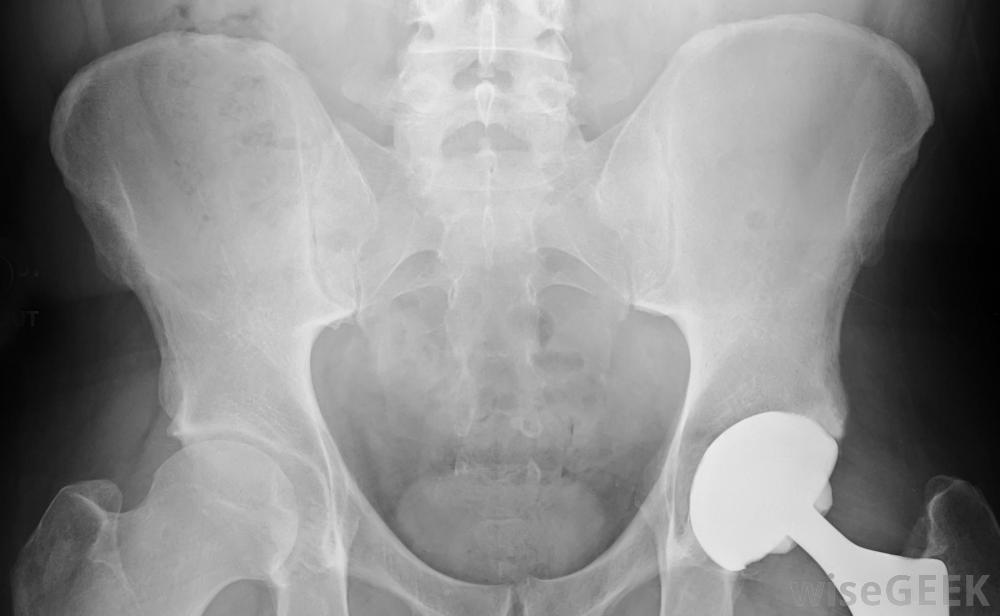

假腿通常是指用来替换受损部分的假肢大多数人想到的是假肢或假肢,但身体的其他部位也可以用假肢来代替。比如牙齿,可以用假牙代替。

假肢设备也为截肢患者提供了更好的生活质量。有一些替代手,可以抓住物品,让患者更轻松地完成日常任务。假腿可以帮助患者在不使用轮椅的情况下再次行走。所有这些都可以帮助患者生活得比他们可能经历的更充实、更有成效。

假腿使截肢者提高了行动能力和独立性。